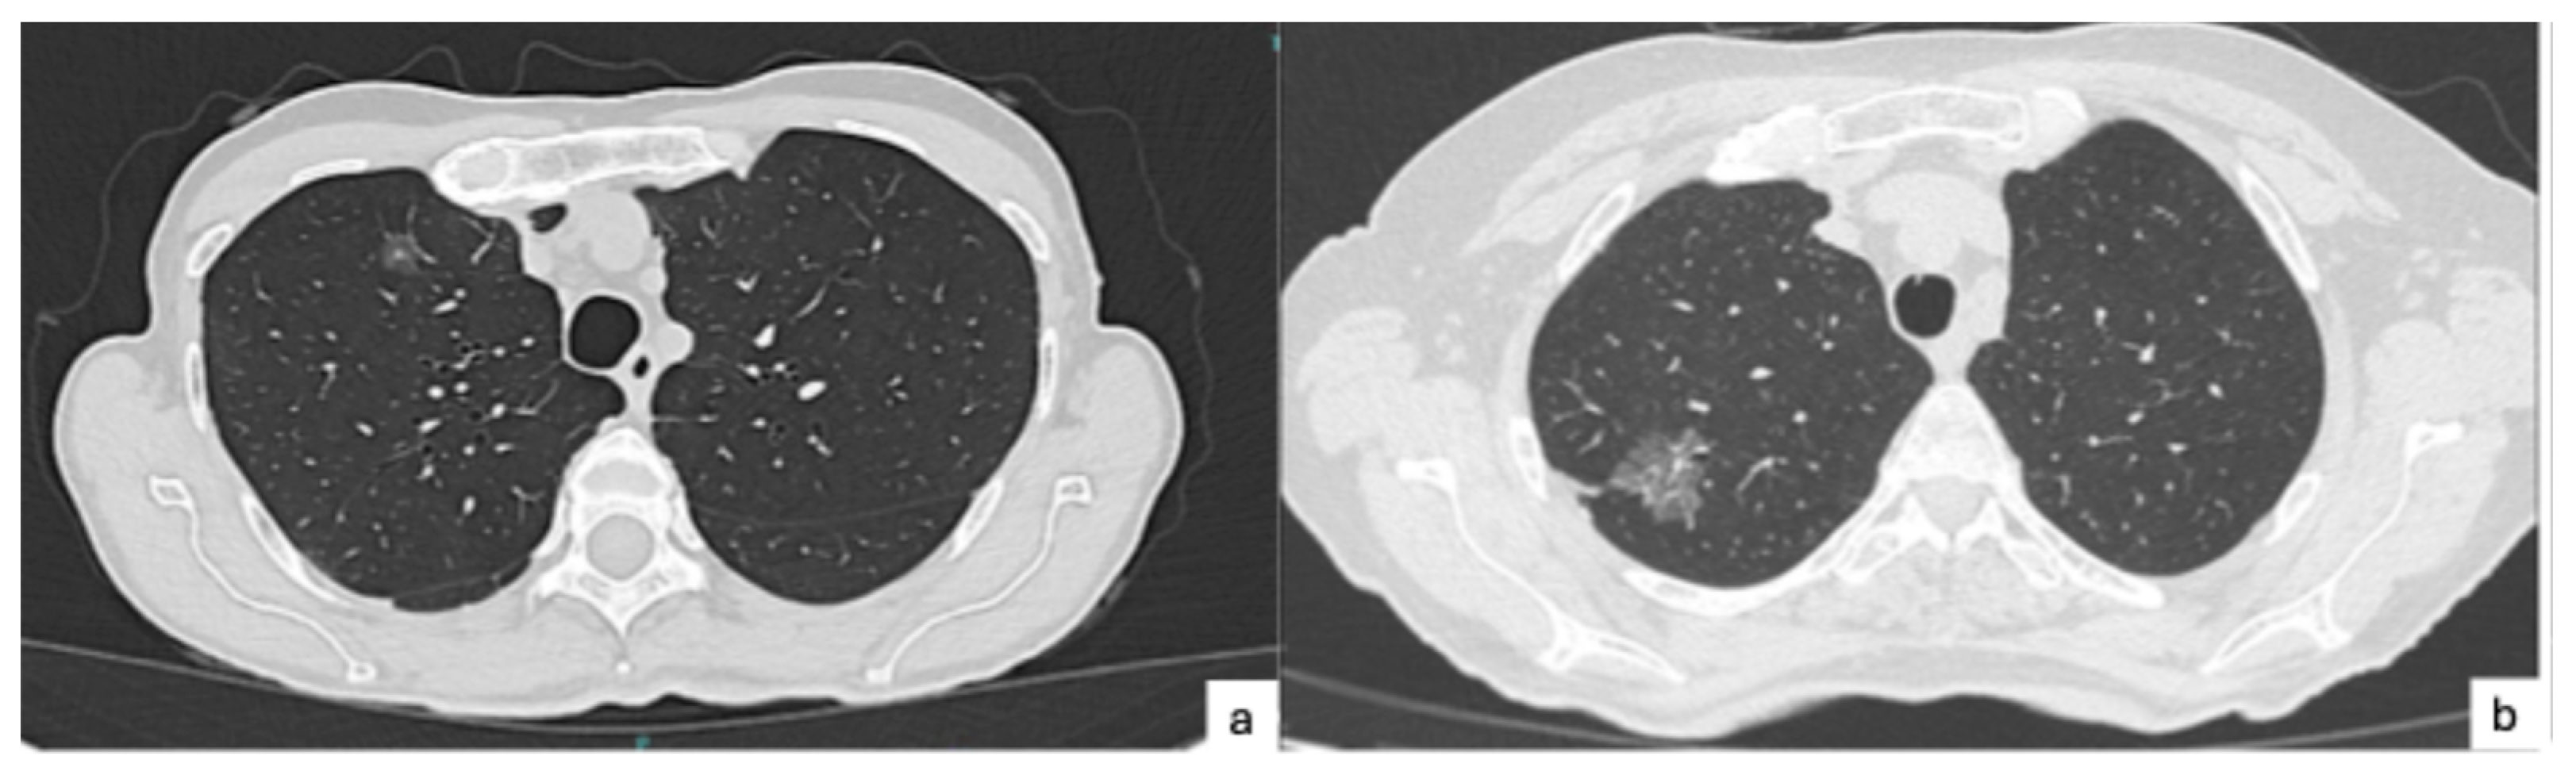

- Toyokawa, G.; Yamada, Y.; Tagawa, T.; Kamitani, T.; Yamasaki, Y.; Shimokawa, M.; Oda, Y.; Maehara, Y. Computed tomography features of resected lung adenocarcinomas with spread through air spaces. J. Thorac. Cardiovasc. Surg. 2018, 156, 1670–1676.e4. [Google Scholar] [CrossRef]

- Kim, S.K.; Chung, M.J.; Kim, T.S.; Lee, K.S.; Zo, J.I.; Shim, Y.M. Lung Adenocarcinoma: CT Features Associated with Spread through Air Spaces. Radiology 2018, 289, 831–840. [Google Scholar] [CrossRef] [PubMed]

- Kameda, F.; Kunihiro, Y.; Tanabe, M.; Nakashima, M.; Kobayashi, T.; Tanaka, T.; Hoshii, Y.; Ito, K. Qualitative and Quantitative Computed Tomography Analyses of Lung Adenocarcinoma for Predicting Spread Through Air Spaces. Tomography 2025, 11, 76. [Google Scholar] [CrossRef]

- Qin, L.; Sun, Y.; Zhu, R.; Hu, B.; Wu, J. Clinicopathological and CT features of tumor spread through air space in invasive lung adenocarcinoma. Front. Oncol. 2022, 12, 959113. [Google Scholar] [CrossRef] [PubMed]

- Zhang, Z.; Liu, Z.; Feng, H.; Xiao, F.; Shao, W.; Liang, C.; Sun, H.; Gu, X.; Liu, D. Predictive value of radiological features on spread through air space in stage cIA lung adenocarcinoma. J. Thorac. Dis. 2020, 12, 6494–6504. [Google Scholar] [CrossRef]